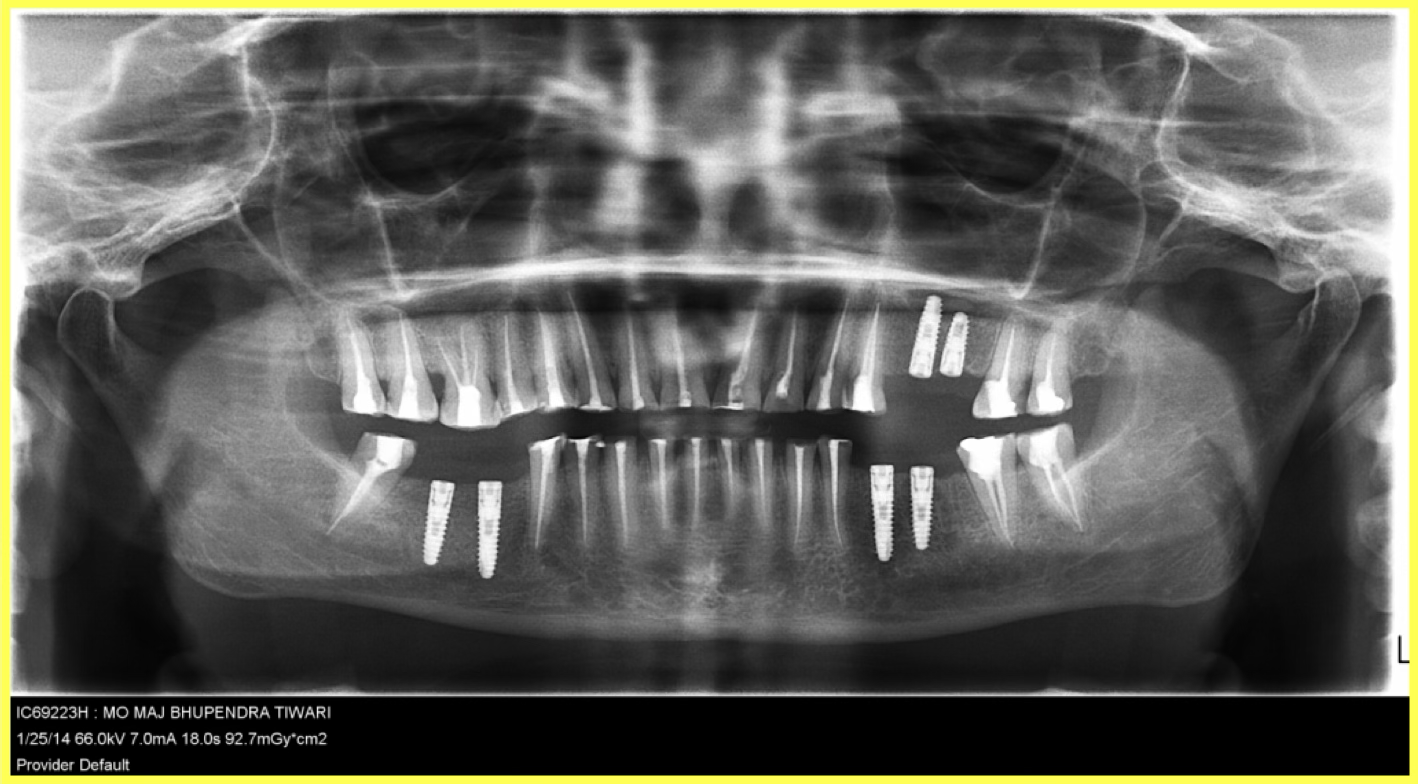

Initial condition

A 57-year-old female patient visited our dental center complaining of multiple missing and attrited teeth. On examination, patient had missing teeth 25, 26, 35, 36, 45 & 46 with grade 3 attrition. Treatment included impression-based muscle deprogrammer, Dio implants placement, PFM crowns for remaining attrited teeth, and delayed implant loading after 3 months.

Comprehensive oral examination with OPG X-ray. Patient presented with multiple missing teeth (25, 26, 35, 36, 45, 46) and severe attrition on remaining teeth. Muscle deprogrammer was fabricated and delivered.